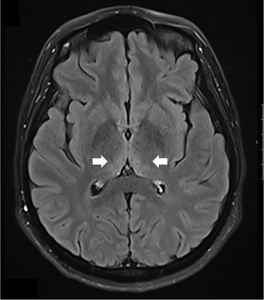

A comprehensive laboratory workup, including human immunodeficiency virus (HIV), Lyme disease serology, rapid plasma reagin (RPR) test, and viral hepatitis panel, was negative. The urine toxicology screen was positive for cannabinoids and amphetamines. Magnetic resonance imaging (MRI) of the brain demonstrated increased T2 signal intensity in the bilateral medial thalami with no involvement of the mamillary body (Figure 1). There was no evidence of optic neuritis, demyelinating lesions, meningeal enhancement, mass effect, or hemorrhage. MRI of the spine showed no active or chronic spinal cord lesions. Nerve conduction studies (NCS), along with serum testing for anti-ganglioside GM1 and anti-GQ1b antibodies, were normal. These tests were conducted to rule out atypical forms of demyelinating neuropathies in light of the patient’s hyporeflexia. Given the clinical presentation and imaging findings, a lumbar puncture (LP) was not performed, as there was no suspicion of infectious, demyelinating, or vascular pathology. The diagnosis of Wernicke’s encephalopathy was confirmed by a low whole blood thiamine level (7 nmol/L; reference range: 8–30 nmol/L), measured using liquid chromatography and mass spectrometry. Quantitative assays of other vitamins (B12, folate, Vitamin A, D, E and K) were within normal limits.

The patient was started on high-dose intravenous thiamine therapy, following established guidelines for the management of Wernicke’s encephalopathy. Based on recommendations from the European Federation of Neurological Societies (EFNS), she received 500 mg of intravenous thiamine every 8 hours for 3 days to rapidly replenish thiamine stores and prevent further neurological deterioration. This was followed by a maintenance dose to support continued recovery and prevent relapse. As her symptoms improved, particularly nausea and abdominal discomfort, she was able to tolerate oral intake. Her diet was gradually advanced to a standard oral regimen as clinical stability was achieved. Repeat MRI brain showed resolution of thalamic hyperintensities at 3 months follow-up (Figure 2)